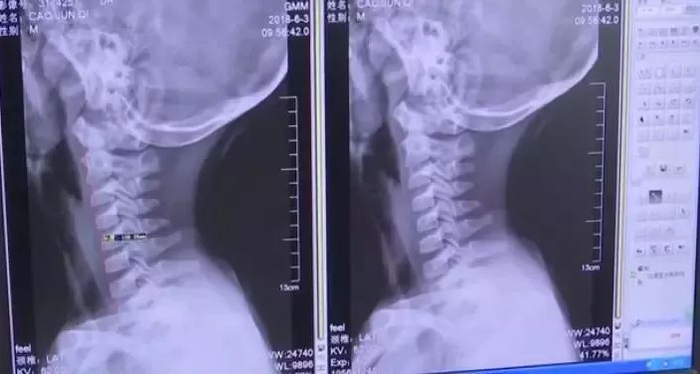

经过CT检查发现,这名9岁男童的颈椎出现问题。人的颈椎通常有前曲的弧度,而他的颈椎变成了一条直线!

生理弧度曲直了,容易影响肌肉血液循环的供应。从而感觉不适。经了解,这名男童一年来经常低头长时间玩手机。